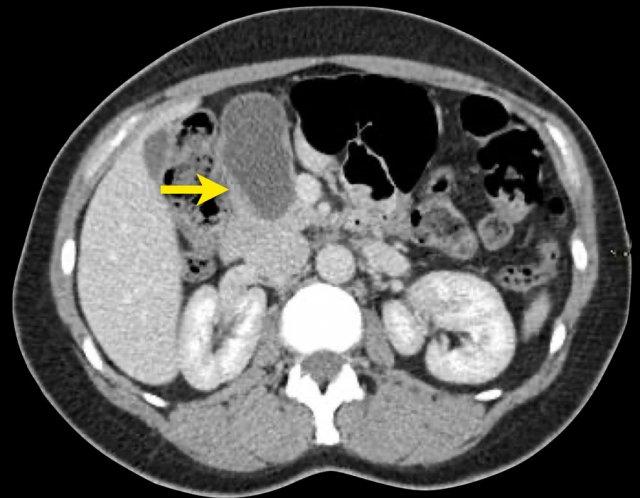

Hình CT bên trái là của một bệnh nhân có tiền sử viêm tụy.

Có hai nang đơn ngăn hay nang đơn giản.

Lưu ý thêm hình ảnh thâm nhiễm mỡ sau phúc mạc bên phải.

Chẩn đoán có khả năng nhất là nang giả.

Hình CT bên phải cho thấy một nang ở đuôi tụy ở một phụ nữ 36 tuổi, được phát hiện tình cờ qua siêu âm.

Nang có bờ dày không đều và chứa các thành phần đặc ‘không phụ thuộc trọng lực’.

Chẩn đoán có khả năng nhất là u nang tân sinh.